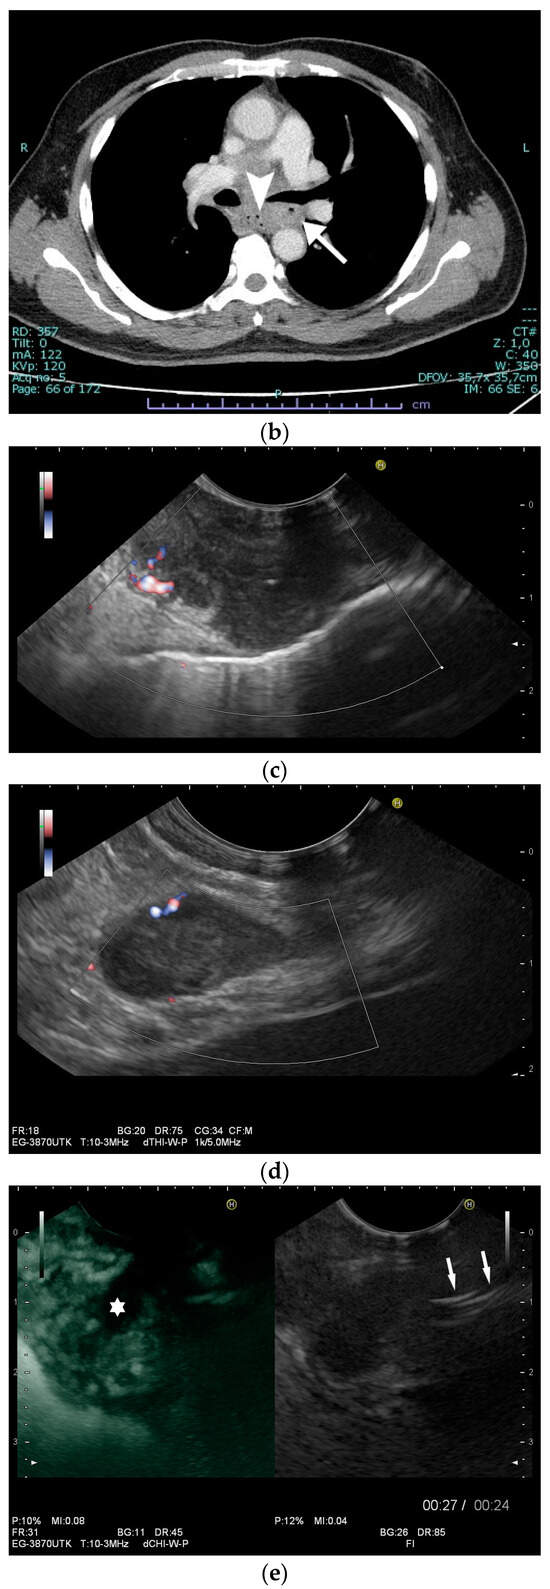

Figure 5.

Pancreatic tuberculosis. Plump large pancreas. There is a lesion with a thick echogenic capsule and hyperechogenic and anechoic contents (between the markers) at the head of the pancreas. This finding was evaluated as a caseous abscess in a patient with tuberculosis.